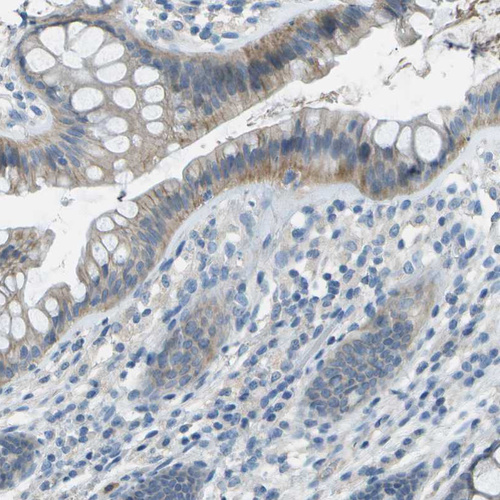

Immunohistochemical staining of human cerebellum shows strong cytoplasmic positivity in Purkinje cells.